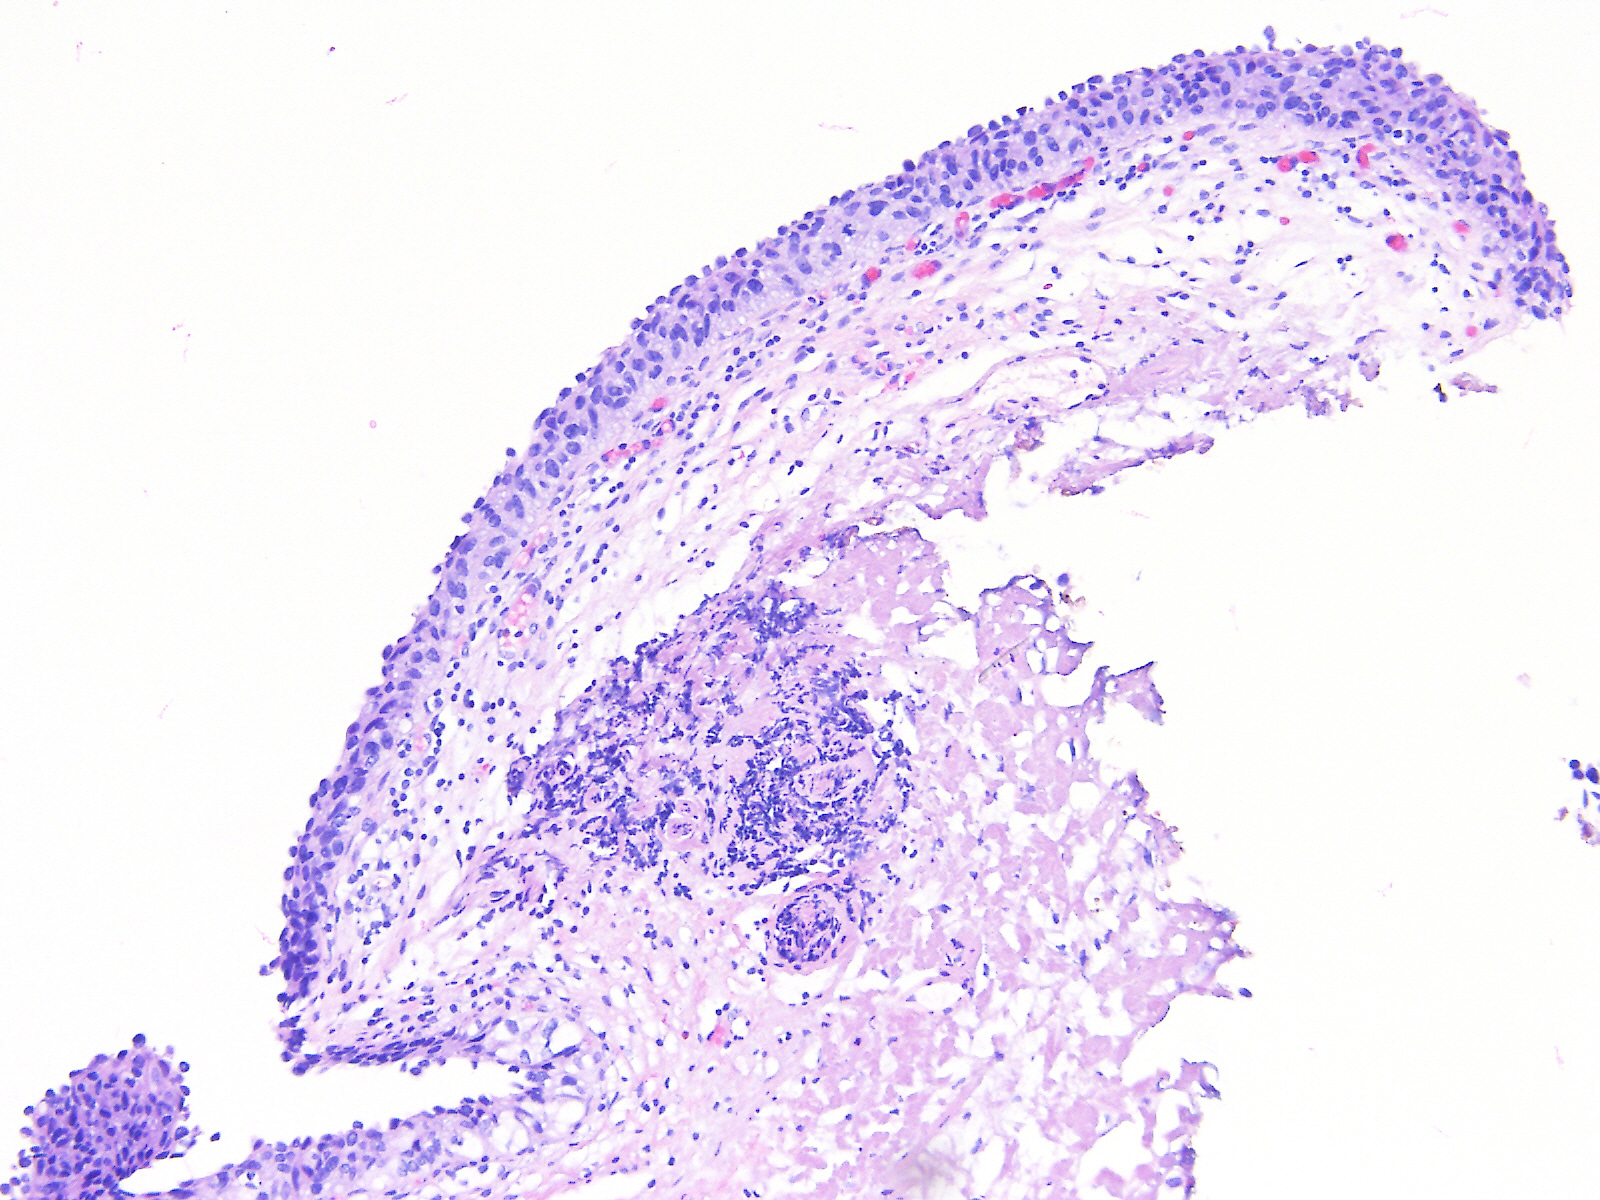

Consensus grade: Carcinoma in situ (CIS)

A 60-year-old female underwent a bladder cystoscopy and biopsy of a 2-cm erythematous lesion at the right posterior bladder wall. About 5 years ago, she was diagnosed with pT1 bladder urothelial carcinoma treated with intravesical therapy.